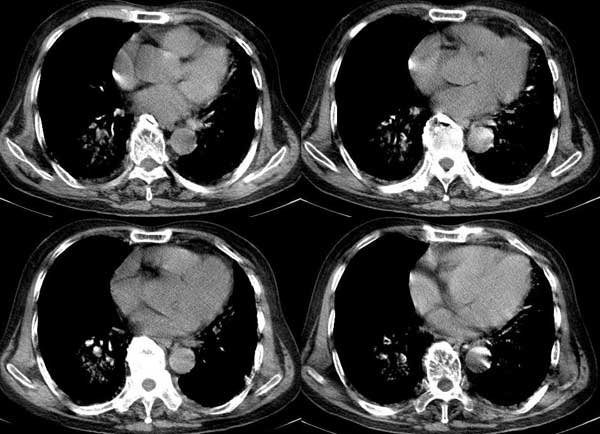

以下是引用dalianren在2006-7-20 21:23:00的发言:[br]我考虑是肺泡蛋白沉积症:典型表现为两肺内散在片状\"磨玻璃\"样混浊区呈地图样分布.

以下是引用lj0804在2006-7-21 12:57:00的发言:[br]支持[br]我考虑是肺泡蛋白沉积症:典型表现为两肺内散在片状\"磨玻璃\"样混浊去呈地图样分布.